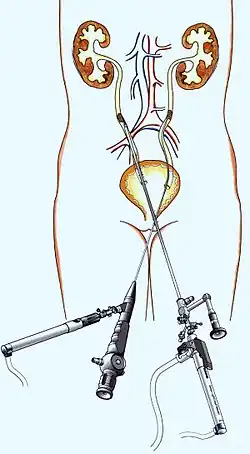

Ureterorenoskopische Steinentfernung (URS)

Eine solche operative Methode wird bei Harnleitersteinen angewendet. Ein dünnes Rohr wird mit einem optischen Instrument (ähnlich wie bei einer Blasenspiegelung) über die Harnröhre in die Blase und weiter in den betroffenen Harnleiter eingeführt. Über den Arbeitskanal des optischen Instruments lassen sich unterschiedliche Geräte zur Zertrümmerung und Entfernung der Harnleitersteine einführen. Dies können Ultraschall-, Laser-, spezielle Sonden oder Zangen sein.